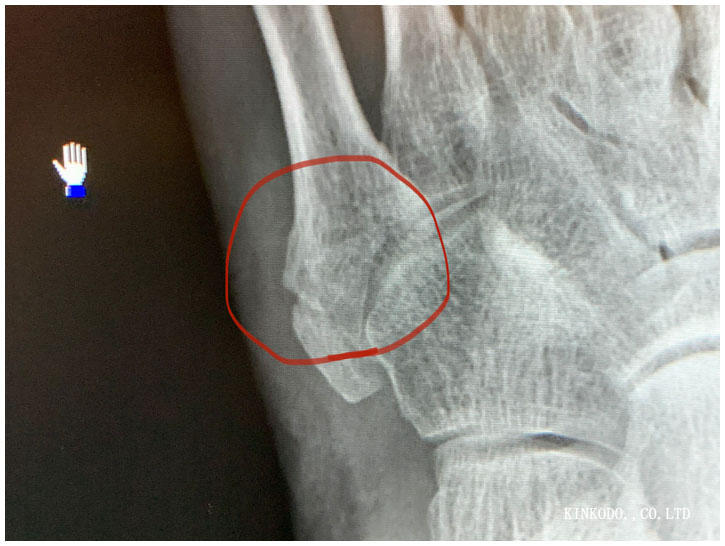

そして今日。

この丸の部分。素人が見てもくっついているよね。と思ったら。

確かにモヤモヤとはしているけど、まだ仮骨はできていないようで、この後エコーで見て貰ってもまだ見えないとのこと。